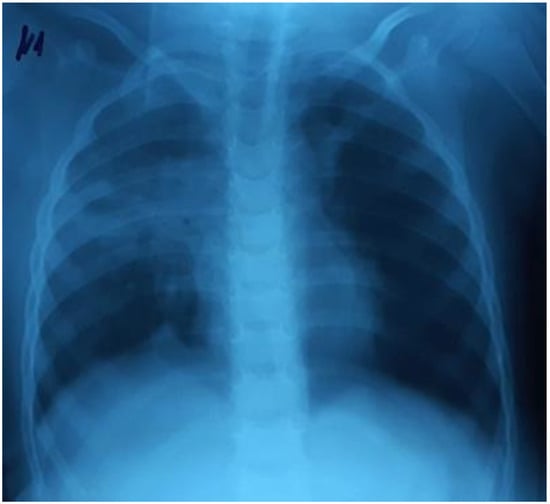

A three-year-old girl (body weight 15 kg) was admitted to the ICU with severe signs of RF. Physical examination revealed shortness of breath, respiratory rate (RR) 72 /min, retraction of intercostal spaces, heart rate (HR) 170/min, sinus tachycardia, SpO2 87%, and body temperature 36.8 °C. Crackles on both sides of the lungs were detected during the auscultation. The chest radiography revealed right-sided focal pneumonia (Figure 1).

Figure 1.

Right-sided focal pneumonia.